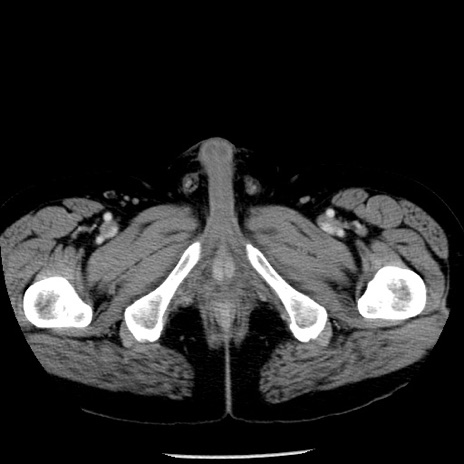

症例29(横断像)

【症例】40歳代男性

【現病歴】2日前から胃痛あり。徐々に周期的な激痛に変化した。本日になっても激痛があるため受診。

【身体所見】意識清明、BT 38-39℃台あり、腹部:膨満、やや硬、右下腹部に圧痛あり。

【データ】WBC 8500、CRP 23.26